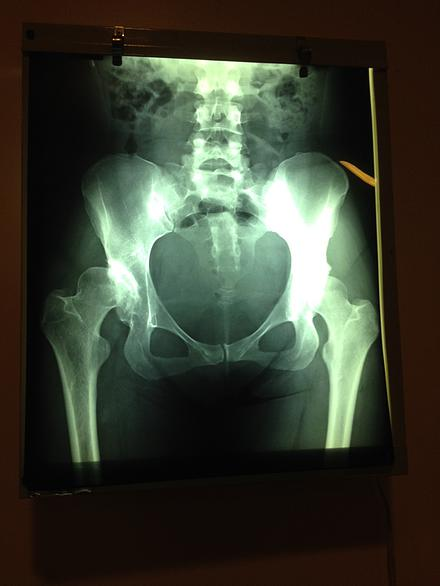

Improvisation…that is the word of the day; whether you talk to the volunteers from Santa Ines or those from the military hospital. In an unfamiliar environment, where our medical professionals are intent on maintaining the highest standard of care possible, there are a few hurdles to overcome as the patient processing is organized, OR set up and each volunteer is locating the resources they need to do their job properly. Although the day got off to a slow start and did become a late evening for some, it all came together well; five hips were completed, two hernias repaired (our hopeful 3 year old hernia did not show!) and seven cataract patients treated – a great first day – a great group of volunteers – cohesive, organized and innovative.